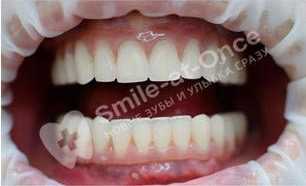

Чорный Станислав Владимирович: портфолио (25)

Имплантация

Для восстановления жевательных зубов потребовалось проведение имплантация полной челюсти по причине плохого состояния зубов на всей челюсти.